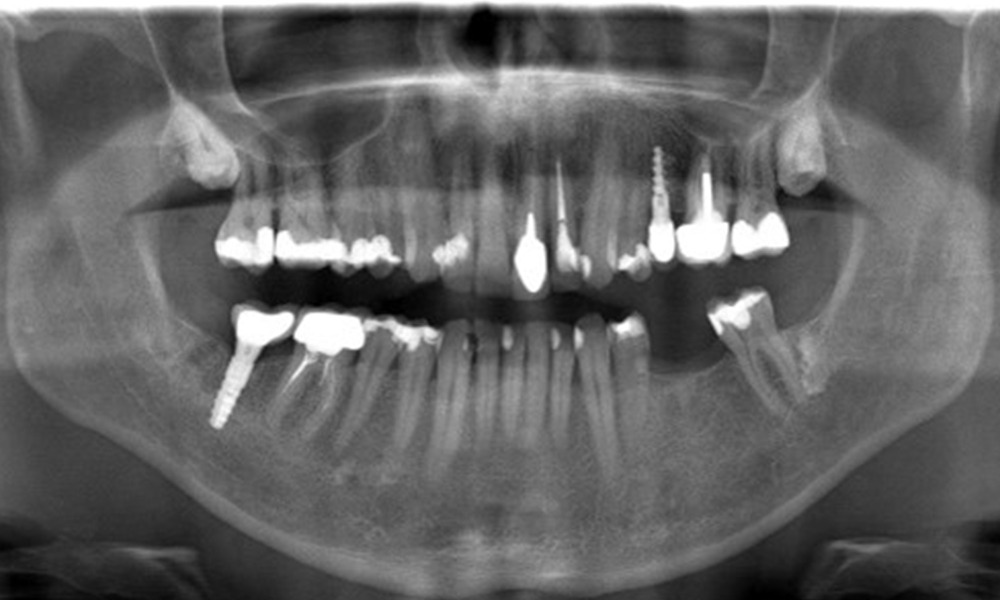

OPG: 29/02/2024

X-ray images (or bitewing X-rays)

X-ray images (or bitewing X-rays) taken on: 18/02/2021

The X-ray image shows the bone loss

The X-ray images show the bone loss.